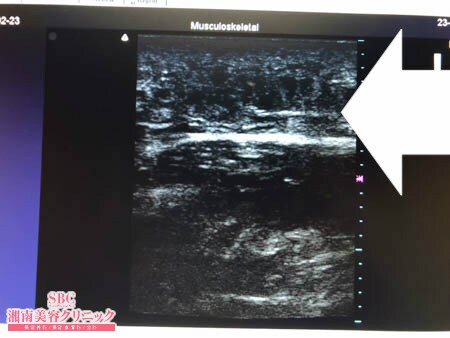

No.249901【脂肪吸引】【動画あり】湘南美容外科脂肪吸引最高責任者である竹田先生による脂肪吸引のフォトギャラリー!他院の再手術!スタッフさんの背中の脂肪吸引!術中3Dタッチビュー・左肩甲骨横

まずは術中劇的変化を紹介しましょう。